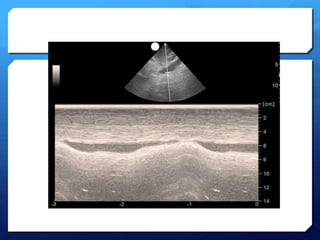

the "seashore sign" (Fig.3).

Absent lung sliding

Exaggerated horizontal artifacts

Loss of comet-tail artifacts

Broadening of the pleural line to a band

The key sonographic signs of

Pneumothorax